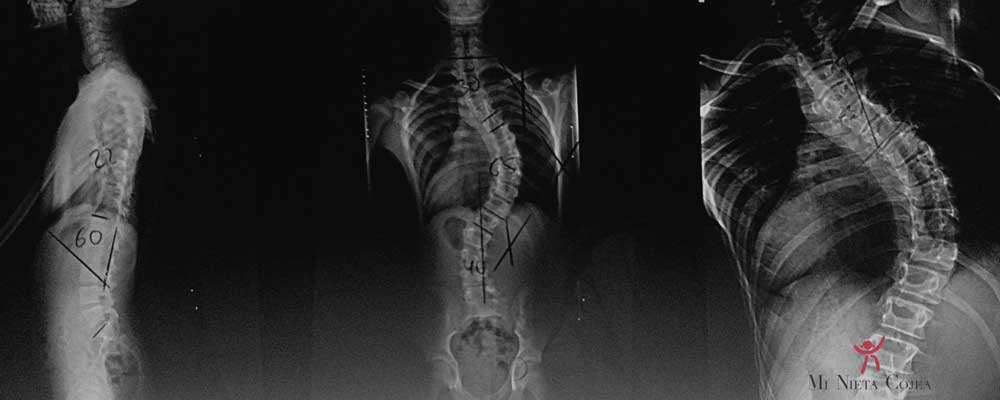

La escoliosis es una espalda torcida… sí, vale. Pero debe de haber algo más detrás de todo esto cuando hay traumatólogos que se dedican exclusivamente a esto. Para la escoliosis hablamos con la perspectiva de ver la espalda de frente (o de espaldas), pero no desde el lado. La espalda normal es recta vista de frente.

Lo que no te esperas es que la rama que usaste para hacer el arco de antes, tenga forma de “S”. Sería una curva “imposible” hacia un lado y hacia el contrario. Y en este caso, en reposo, al ver la espalda de frente tiene la forma de “S” en vez recto como una “I”.

El problema es algo más complejo ya que es tridimensional. De nuevo una comparación mundana para intentar entenderlo: tienes una toalla mojada y la escurres estrujando y estrujando dando más y más vueltas para escurrirla. Llegado un momento con muchas vueltas dadas, la toalla se repliega-se enrosca haciendo curvas como una cola de cerdo. Esas nuevas curvas (3D) que se han formado tras girar y girar la toalla, si les hacemos una foto de frente (las pasamos a una imagen 2D), representan las curvas de la “S” de la escoliosis. Es decir, la escoliosis es una curva 3D que se forma como consecuencia de la rotación de las vértebras de la columna. Lo que pasa es que en la toalla hay que dar muchas vueltas para generar esta nueva curva y en la columna con un cuartito de vuelta ya se enrosca y produce la escoliosis.

Este concepto 3D las pacientes lo comprenden muy bien al comprobar que la rotación es lo que les hace tener las costillas flotantes de un lado más saliditas y la escápula del lado contrario más saliente hacia atrás.